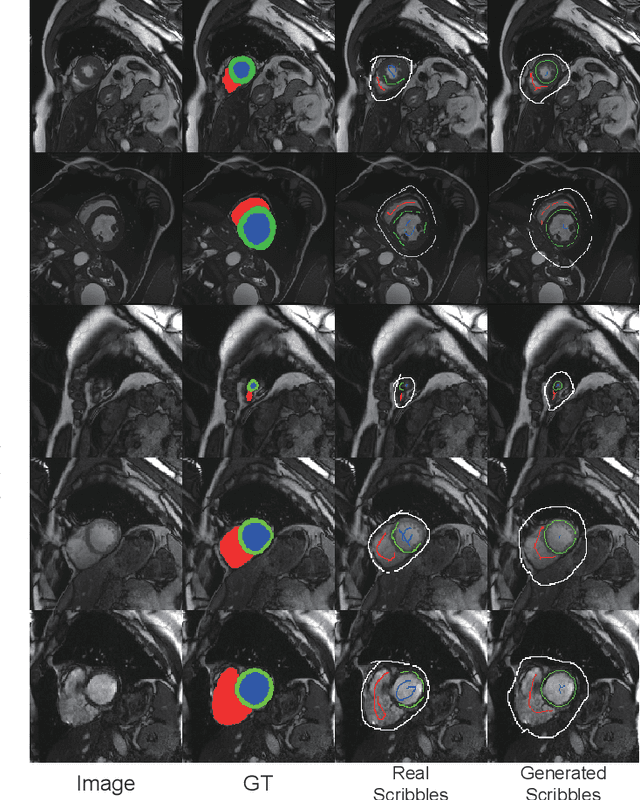

Abstract:Recently, weakly-supervised image segmentation using weak annotations like scribbles has gained great attention in computer vision and medical image analysis, since such annotations are much easier to obtain compared to time-consuming and labor-intensive labeling at the pixel/voxel level. However, due to a lack of structure supervision on regions of interest (ROIs), existing scribble-based methods suffer from poor boundary localization. Furthermore, most current methods are designed for 2D image segmentation, which do not fully leverage the volumetric information if directly applied to each image slice. In this paper, we propose a scribble-based volumetric image segmentation, Scribble2D5, which tackles 3D anisotropic image segmentation and aims to its improve boundary prediction. To achieve this, we augment a 2.5D attention UNet with a proposed label propagation module to extend semantic information from scribbles and use a combination of static and active boundary prediction to learn ROI's boundary and regularize its shape. Also, we propose an optional add-on component, which incorporates the shape prior information from unpaired segmentation masks to further improve model accuracy. Extensive experiments on three public datasets and one private dataset demonstrate our Scribble2D5 achieves state-of-the-art performance on volumetric image segmentation using scribbles and shape prior if available.